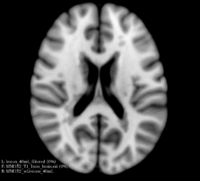

Image:MNI152_lesionload40mL_sag.png|The same MNI152 template with 40mL lesion load simulated lesions (sagittal orientation)